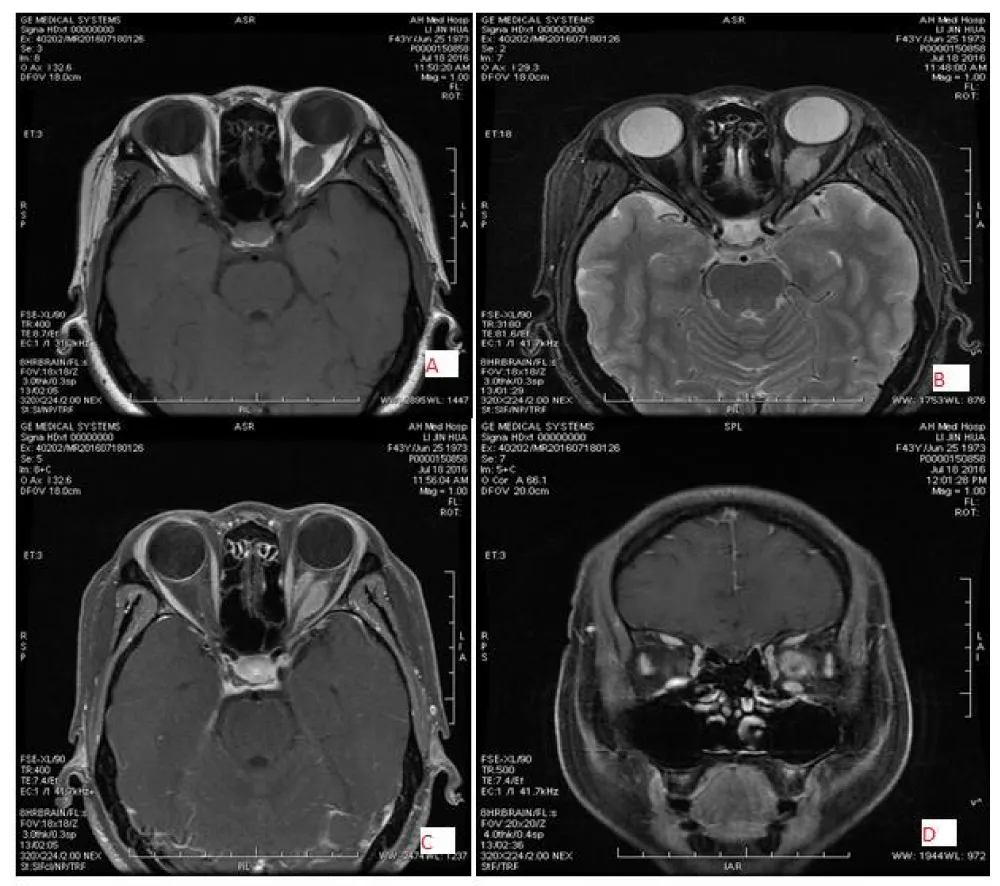

Download Image

Figure 3: 44-year-old female patient with right-sided schwannoma, located in the intraconal and inferolateral region with well-defined margin and oval shape, low signal intensity on T1WI (A) and slightly high signal intensity on T2WI (B&C) and marked homogeneous enhancement (D).